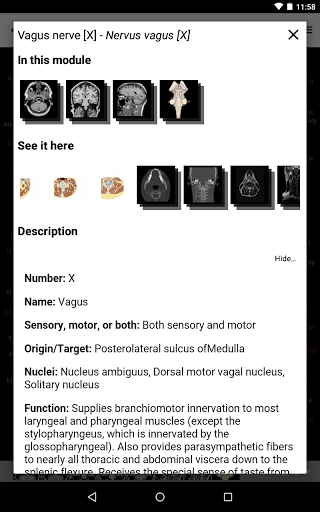

* تحسين رؤية تعريفات الأجزاء التشريحية

* تصفح بين الأجزاء التشريحية باستخدام روابط الوصف

- يتم الآن عرض المصطلحات المتعلقة بالهيكل التشريحي في عرض التفاصيل - تمت إضافة